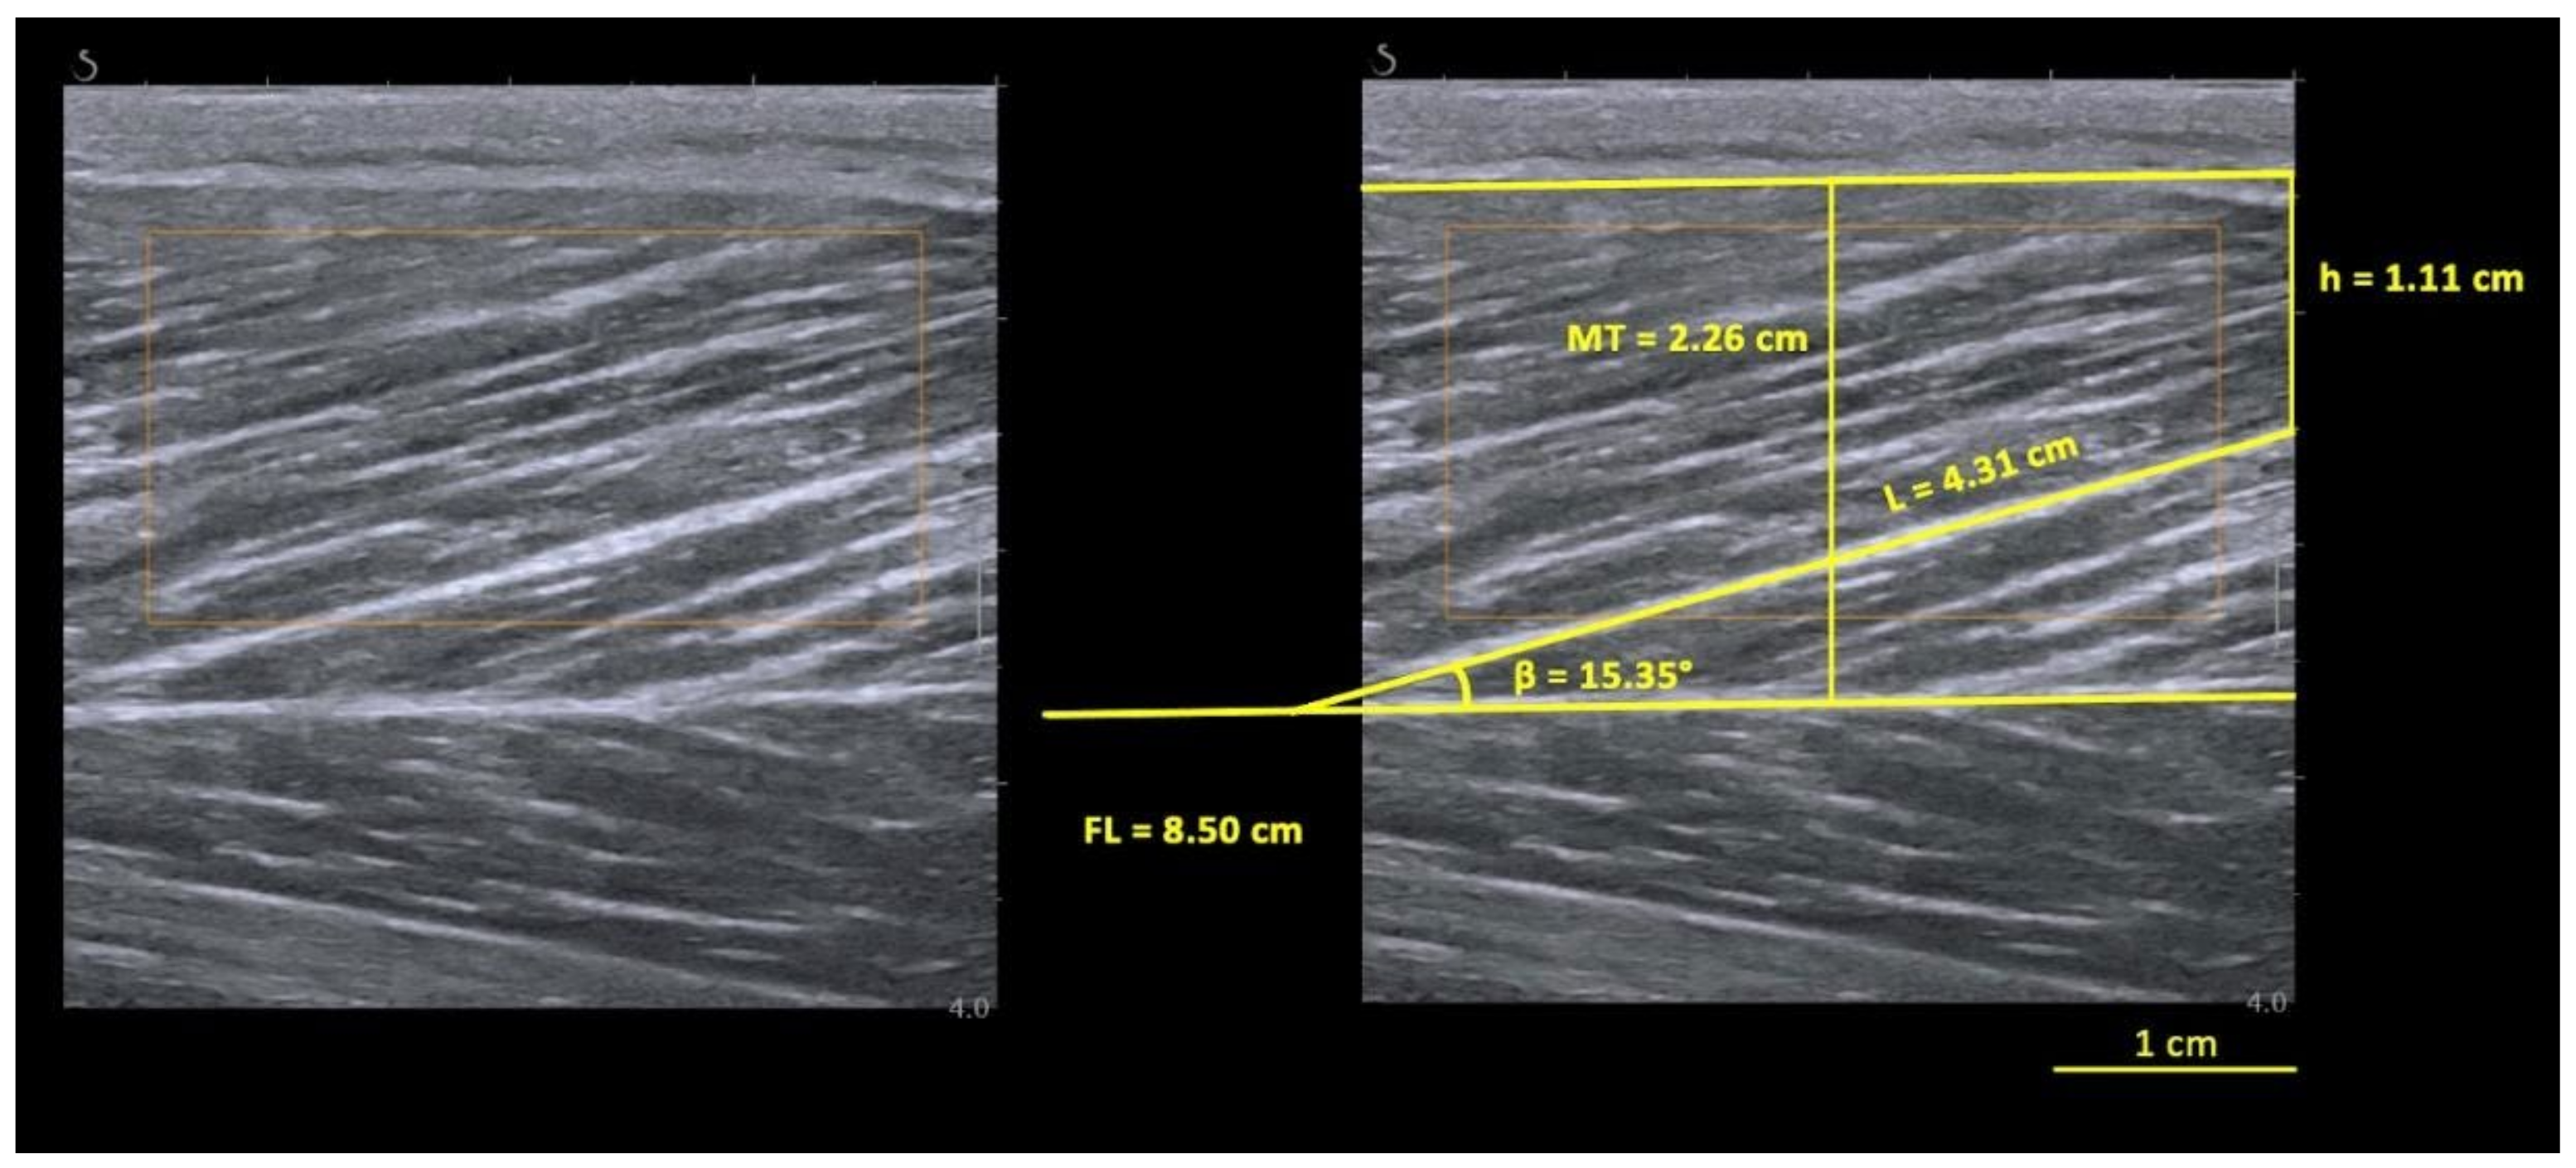

2.2. BFlh Architecture Assessment